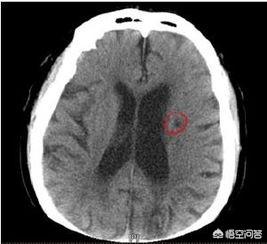

脳梗塞発症後24〜48時間後に脳のCT検査を行うと、対応する部位に境界のはっきりしない低密度の病巣が認められ、何らかの占拠作用がある可能性がある。脳磁気共鳴(MRI)検査では、病変部のT1低信号と加重画像のT2高信号によって示される脳梗塞を早期に発見することができ、MRIはより小さな梗塞病変を検出することができる。

空洞性脳梗塞の病変は小さく、専門医でなければ容易に認識できない。